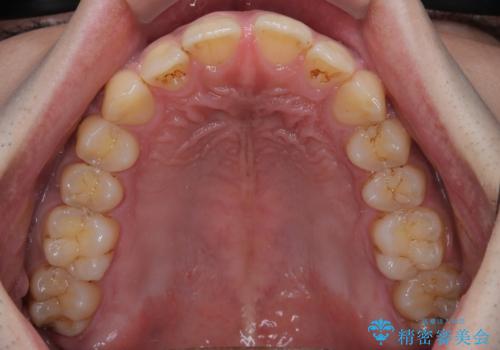

- 上の前歯の正中離開(すきっ歯)と、下顎前歯部の叢生(デコボコ)を主訴に来院された患者様の症例です。

「目立ちにくい装置で治療したい」とのご希望があり、透明のマウスピース矯正であるインビザラインを用いて矯正治療を行いました。

インビザラインは装置が透明で、周囲に気づかれにくいことが大きなメリットです。

取り外しもできるため衛生面でも安心して治療を進めていただけました。